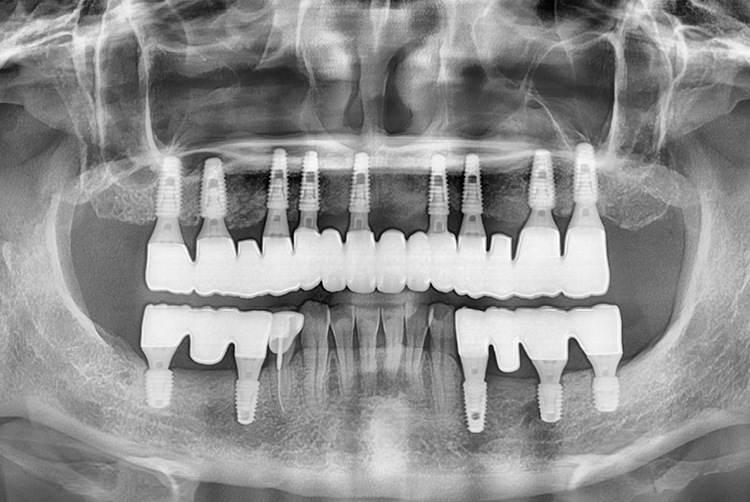

[임플란트] 임플란트

치료전 : 2018-11-02

22.02.26.jpg

치료후 : 2022-02-26

세종치과는 많은 환자와 다양한 케이스를 바탕으로 항상 편안한 임플란트 수술을 제공하고자 노력하고,

오래동안 튼튼히 쓸 수 있는 임플란트 수술을 가장 큰 목표로 삼고 있습니다